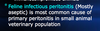

Uterine Rupture caused by Pyometra can lead to _____

Septic Peritonitis